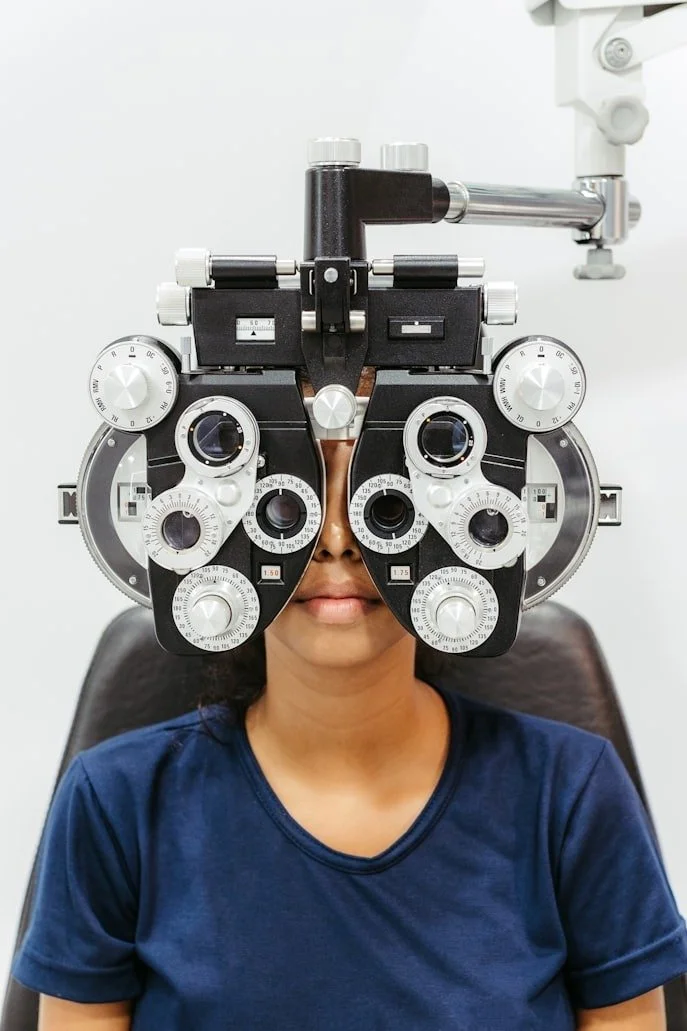

Thoughtful, modern eye care designed around long-term vision and comfort.

Greenwood Village Eye Studio was created with a simple goal: to provide eye care that feels both clinically advanced and genuinely attentive. We believe patients deserve more than a quick vision check — they deserve a clear understanding of their eye health, access to modern diagnostic technology, and a care experience that’s comfortable, thorough, and personalized. Our approach blends preventative screening, detailed evaluations, and solutions tailored to each patient’s visual needs. Whether you’re here for a comprehensive exam, a dry eye evaluation, or a specialty contact lens fitting, we take the time to get it right.

A Comfortable, Modern Exam Experience:

Our testing process uses gentle, modern instrumentation designed to make your visit smooth

and stress-free.